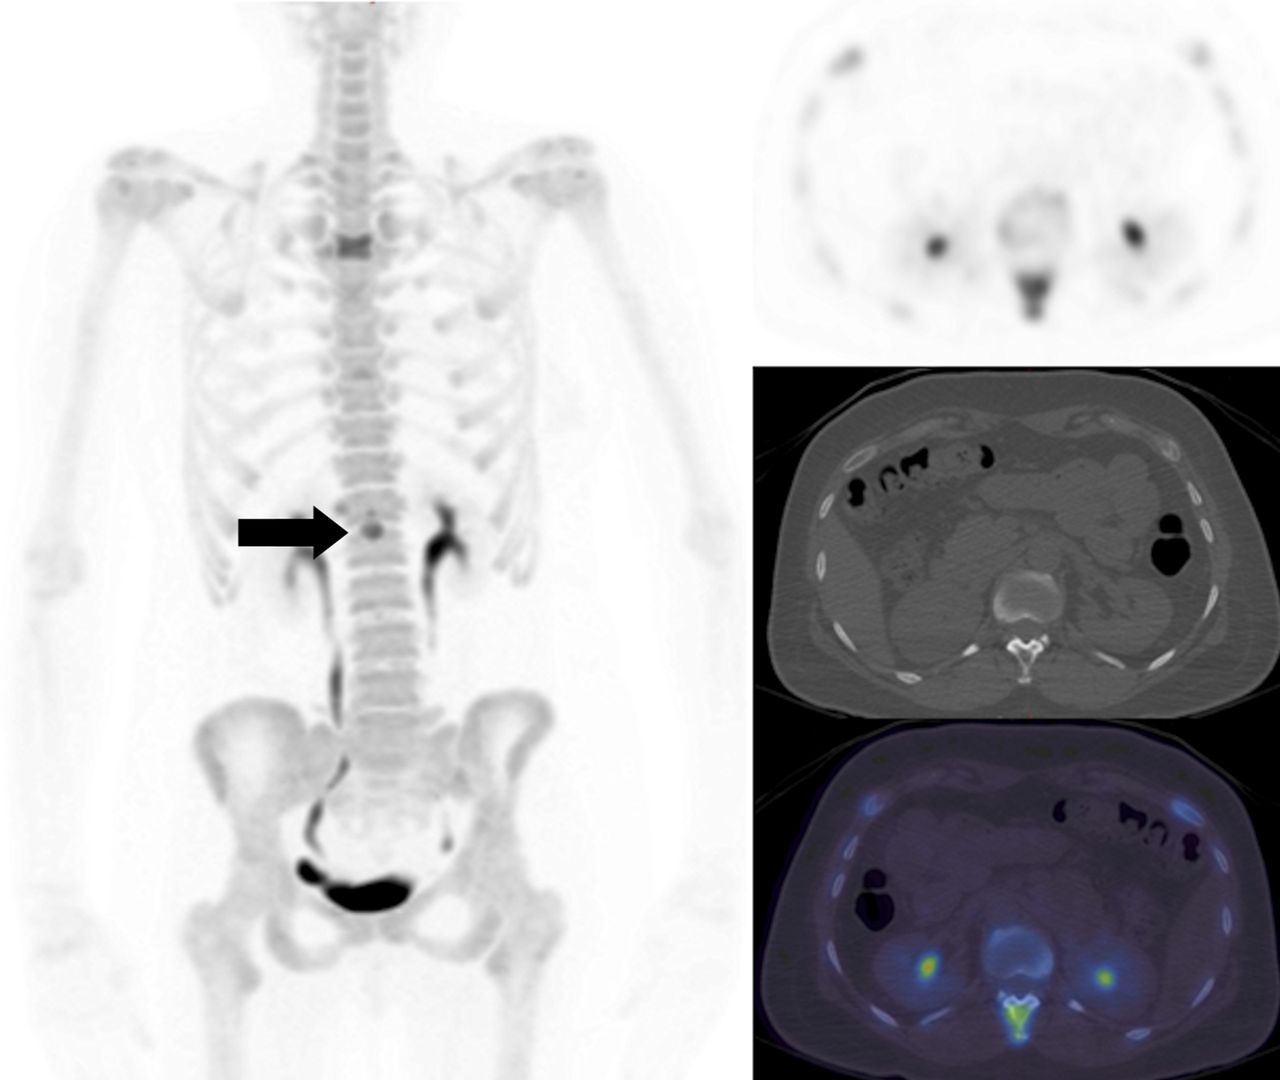

期間限定特別価格 Roentgen Signs 9780721663029 Abdomen: Imaging: Diagnostic in 医学一般の詳細情報

Roentgen Signs in Diagnostic Imaging: Abdomen: 9780721663029。PET Scans Guiding Chemo Boost Remission for Hodgkin Patients。Roentgen Signs in Diagnostic Imaging: The Chest。期間限定割引SW.13 特级黄小米 小米 あわ 粟 健康食糧 粗糧 40038y。 閉じる